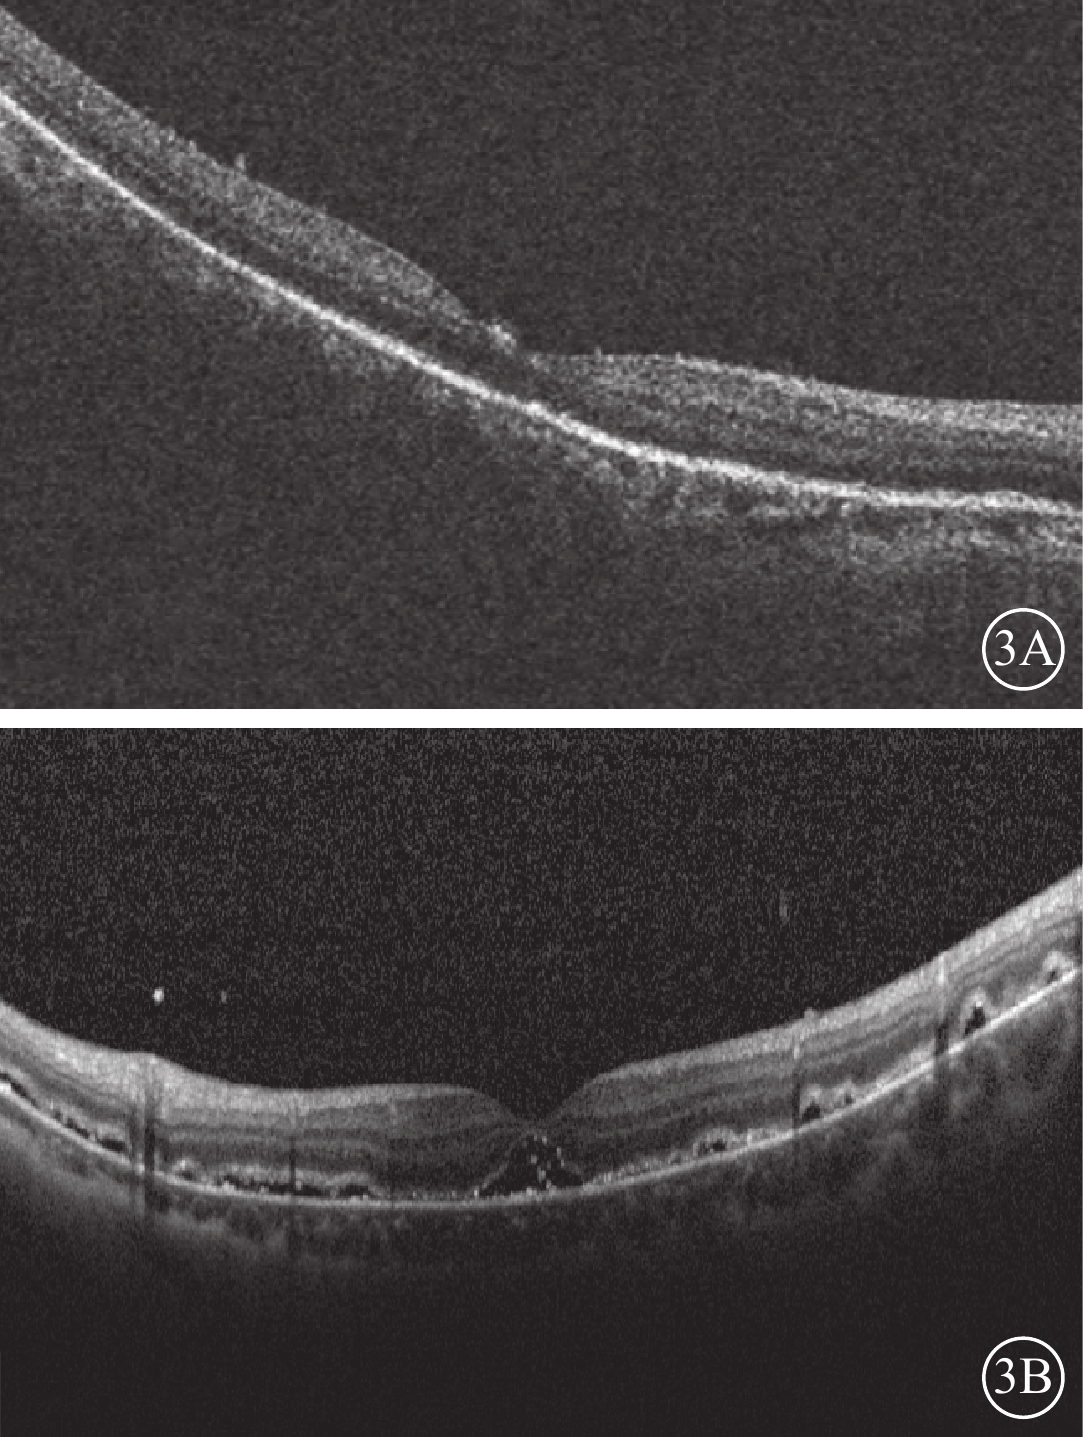

12只眼中,視網膜完全復位(圖3A)6只眼(50.00%),部分復位伴黃斑區視網膜下液(圖3B)4只眼(33.33%),未復位2只眼(16.67%)。視網膜部分復位伴黃斑區視網膜下液患眼原視網膜裂孔均位于脈絡膜墊壓嵴上,裂孔封閉;給予密切隨訪,視網膜下液隨時間延長逐漸吸收。視網膜未復位的2只眼均為高度近視眼,其中1只眼因脫離時間較長已形成3個裂孔且視網膜下見增生條帶,另1只眼為2 DD大小的馬蹄樣裂孔且視網膜脫離范圍累及4個象限;其采用玻璃體切割聯合硅油填充手術或鞏膜外硅膠墊壓手術復位視網膜。

圖3

患眼手術后1周OCT像。3A示黃斑區神經上皮完整復位;3B示視網膜部分復位,黃斑區視網膜下少許積液

圖3

患眼手術后1周OCT像。3A示黃斑區神經上皮完整復位;3B示視網膜部分復位,黃斑區視網膜下少許積液

12只眼中,視網膜完全復位(圖3A)6只眼(50.00%),部分復位伴黃斑區視網膜下液(圖3B)4只眼(33.33%),未復位2只眼(16.67%)。視網膜部分復位伴黃斑區視網膜下液患眼原視網膜裂孔均位于脈絡膜墊壓嵴上,裂孔封閉;給予密切隨訪,視網膜下液隨時間延長逐漸吸收。視網膜未復位的2只眼均為高度近視眼,其中1只眼因脫離時間較長已形成3個裂孔且視網膜下見增生條帶,另1只眼為2 DD大小的馬蹄樣裂孔且視網膜脫離范圍累及4個象限;其采用玻璃體切割聯合硅油填充手術或鞏膜外硅膠墊壓手術復位視網膜。

圖3

患眼手術后1周OCT像。3A示黃斑區神經上皮完整復位;3B示視網膜部分復位,黃斑區視網膜下少許積液

圖3

患眼手術后1周OCT像。3A示黃斑區神經上皮完整復位;3B示視網膜部分復位,黃斑區視網膜下少許積液